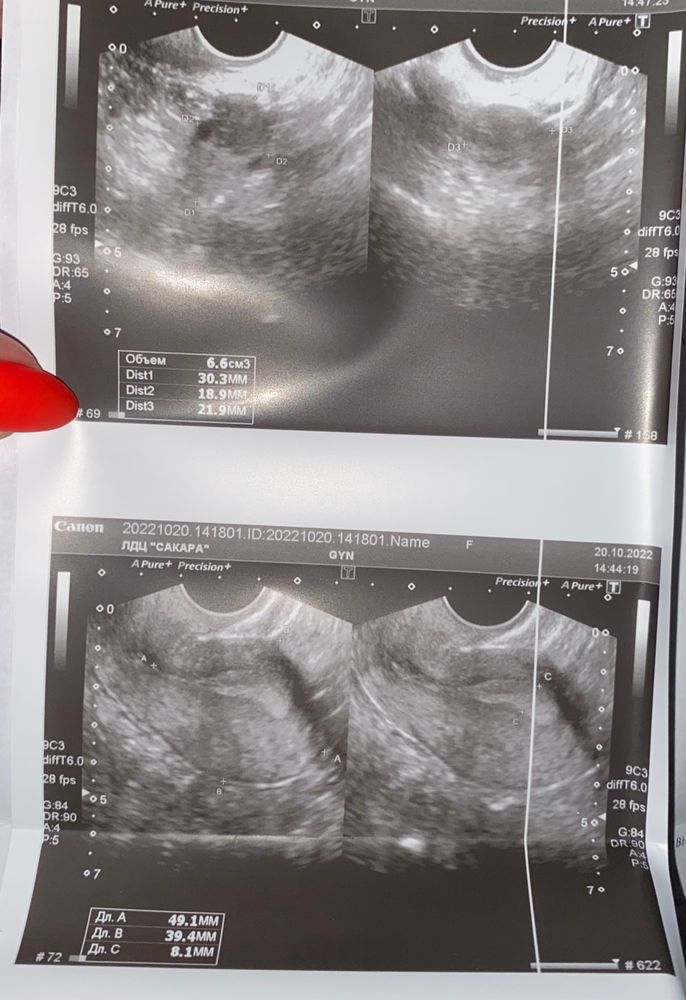

Сходила на узи малого таза ФОТО внутри

На узи она увидела немного выделений и сказала до задержки подождать;если М не придут), но ничего страшного или странного нет. Есть желтое тело, нормальный эндометрий.

Вас смущают эти выделения? По УЗИ всё хорошо, у вас была овуляция, судя по тому, что жидкости нет, то она была около недели назад. Ваши выделения могут быть имплантационным кровотечением. Ещё в рекомендациях стоит хгч и УЗИ через 5-7 . Я бы хгч сдала, а на УЗИ рано будет ещё идти. Удачи вам)).